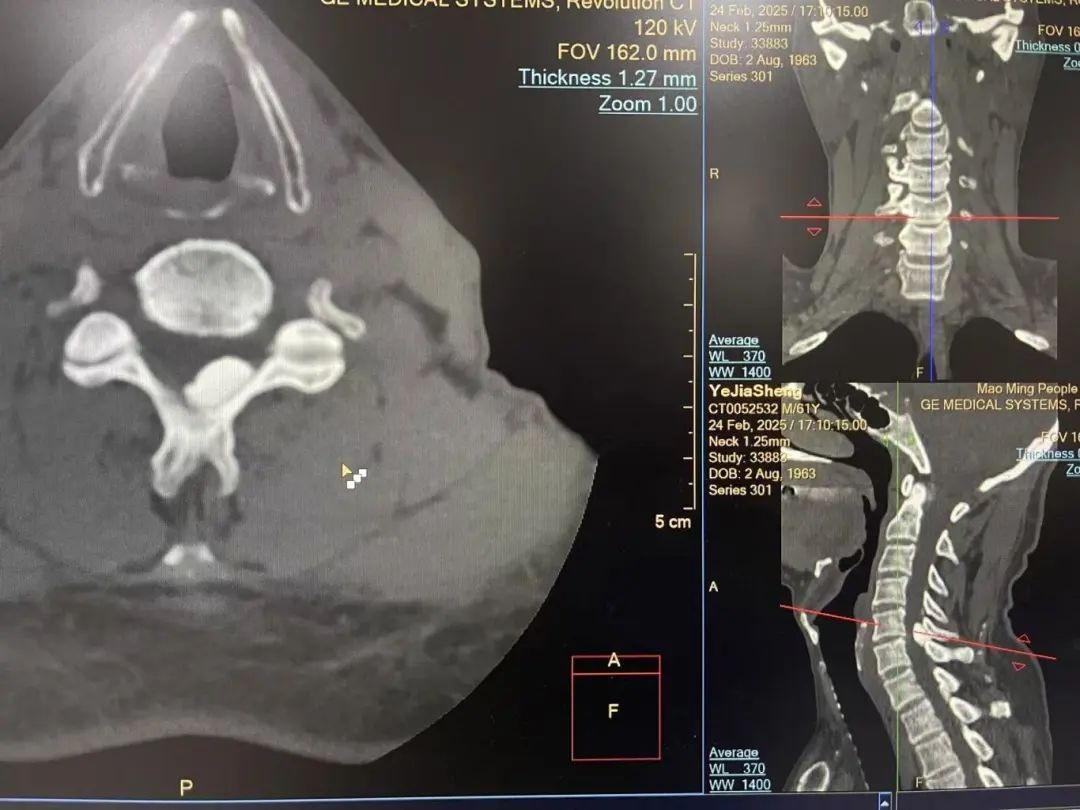

▲术前CT影像

为求治疗,陈伯在家属陪同下来到茂名市人民医院脊柱外二科赵斌修主任医师专家门诊就诊,经详细询问病史与查体,陈伯被确诊为“C5/6右侧黄韧带骨化合并颈椎管狭窄/脊髓半切综合征(不典型)”,急需住院手术治疗,否则若病情继续发展,病人终会因脊髓逐渐受压加重而出现瘫痪。从影像学检查来看,病人颈椎黄韧带钙化灶压迫较大,横截面上已占据相当大的面积,挤压颈髓严重,手术风险极大;赵斌修主任医师坦言:“这类病例若采用以前传统的开放手术,需大范围切开椎板,创伤大、出血多、恢复慢、手术道口容易感染,而且治疗花费大,术中如果稍有不慎可能损伤脊髓,导致病人截瘫的不可逆后果” 。赵斌修主任医师团队反复研讨,最终决定采用当今国际前沿的单侧双通道脊柱内镜技术(UBE)为病人行手术治疗。